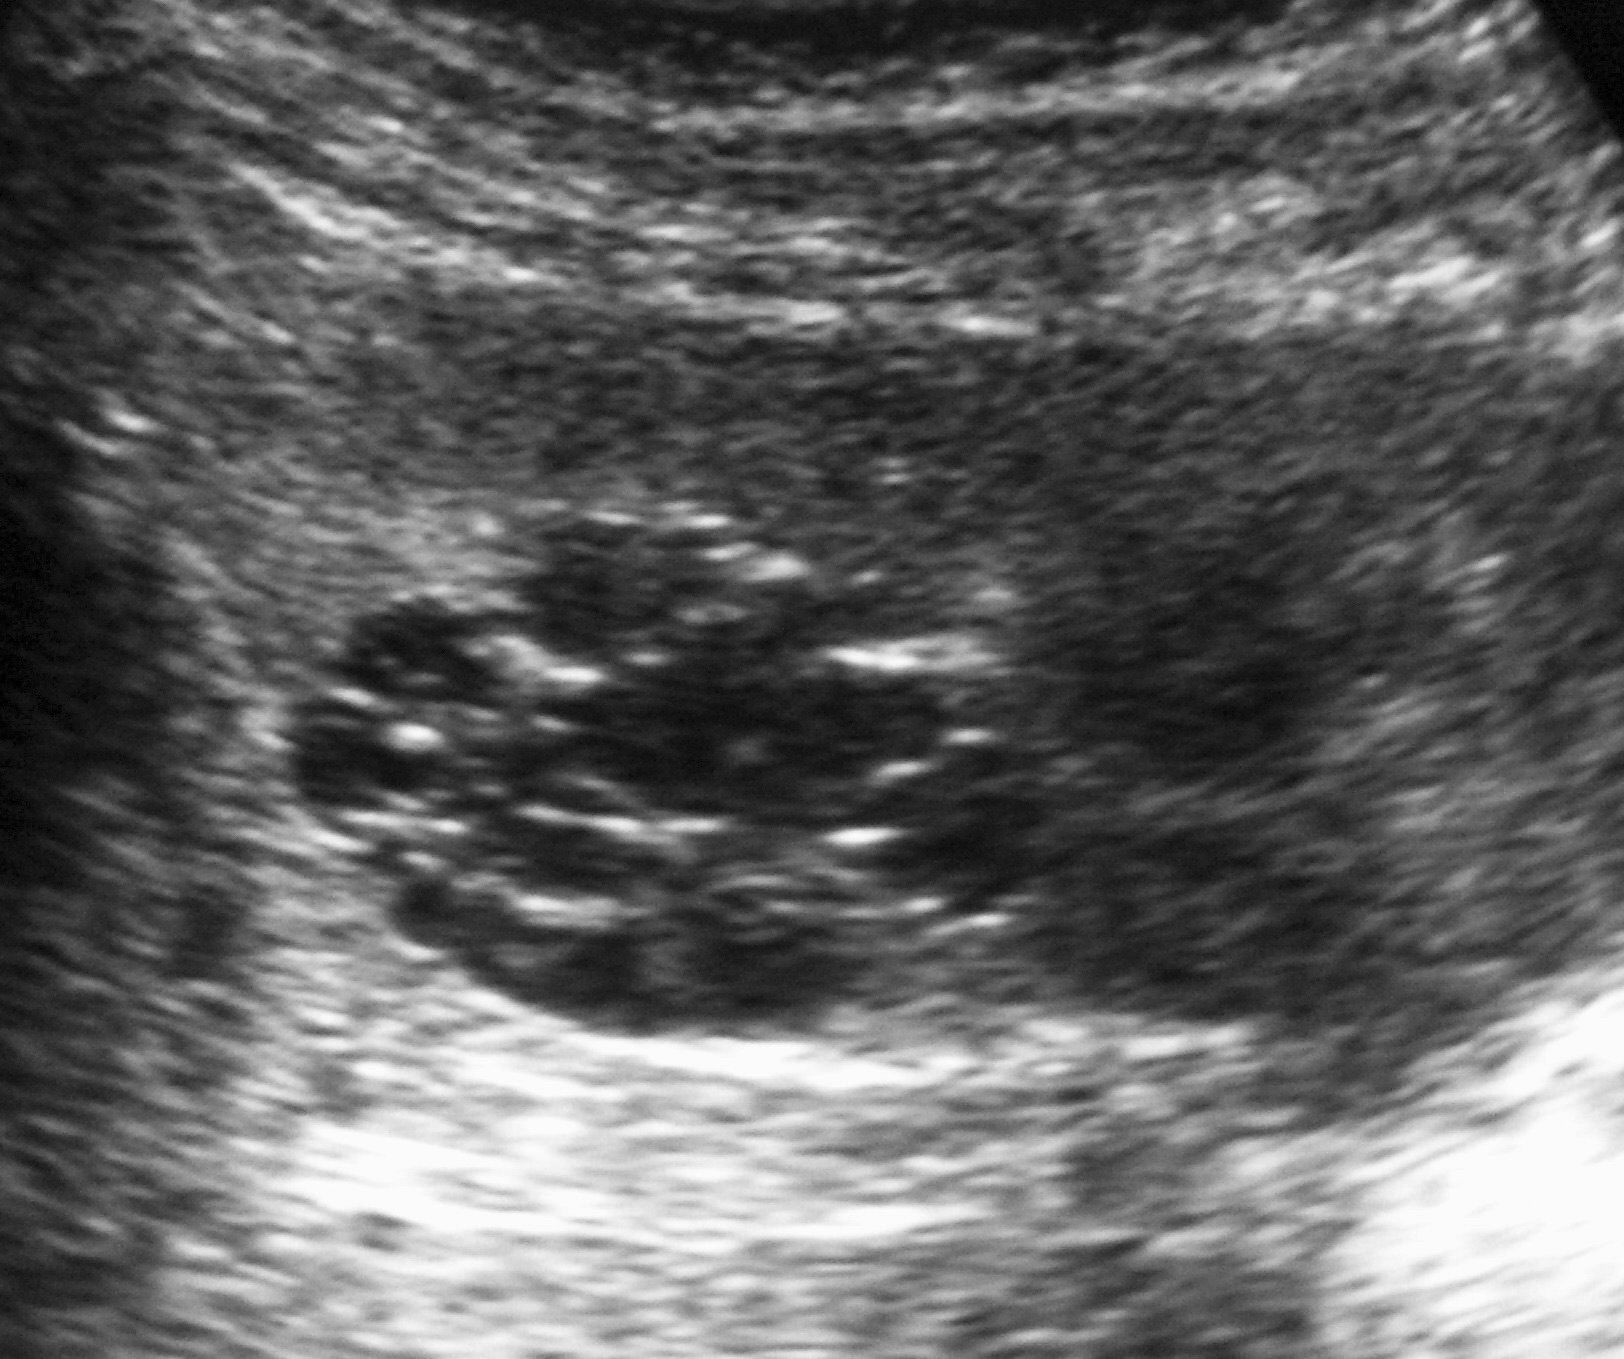

Los pacientes con diagnóstico histológico de tumor quístico multilocular (n = 7) tenían entre 5 meses y 12 años, siendo 4 de ellos varones y 3 mujeres. La clínica inicial fue la de masa abdominal palpable en 5, hematuria en uno y dolor abdominal en el paciente mayor. Se identificaron masas renales bien definidas que presentaban un aspecto quístico, con múltiples loculaciones separadas por septos que mostraban discreto realce (figs. 3 y 4). En un paciente se encontraron focos de blastema en las paredes de los septos en el estudio histológico.

Fig. 4 Tumor quístico multilocular. (A) Ecografía abdominal. Corte renal longitudinal. Masa en tercio medio de riñón derecho, multiquística. (B) Tomografía computarizada abdominal con contraste intravenoso. Corte al nivel de los hilios renales. Cavidades hipodensas, tabicadas. (C) Resonancia magnética T2 coronal. Cavidades hiperintensas separadas por septos hipointensos bien definidos.

Los estudios radiológicos muestran una masa de gran tamaño, encapsulada, con múltiples quistes no comunicantes, que pueden herniarse hacia la pelvis y el uréter y cuyos septos presentan un realce irregular bajo o moderado4,8,9.

Los hallazgos encontrados en los estudios de imagen no permiten la distinción entre nefroma quístico y nefroblastoma quístico parcialmente diferenciado, aunque esto no tiene relevancia de cara al tratamiento, puesto que es el mismo: la excisión quirúrgica6,8,9. Sin embargo, el nefroma quístico parcialmente diferenciado puedemuy bueno tras la nefrectomía.

Sólo en uno de nuestros pacientes se encontraron focos de blastema en el estudio histológico. A un paciente se le realizó tumorectomía y el resto fueron tratados con nefrectomía. Todos ellos quedaron libres de enfermedad tras la cirugía.